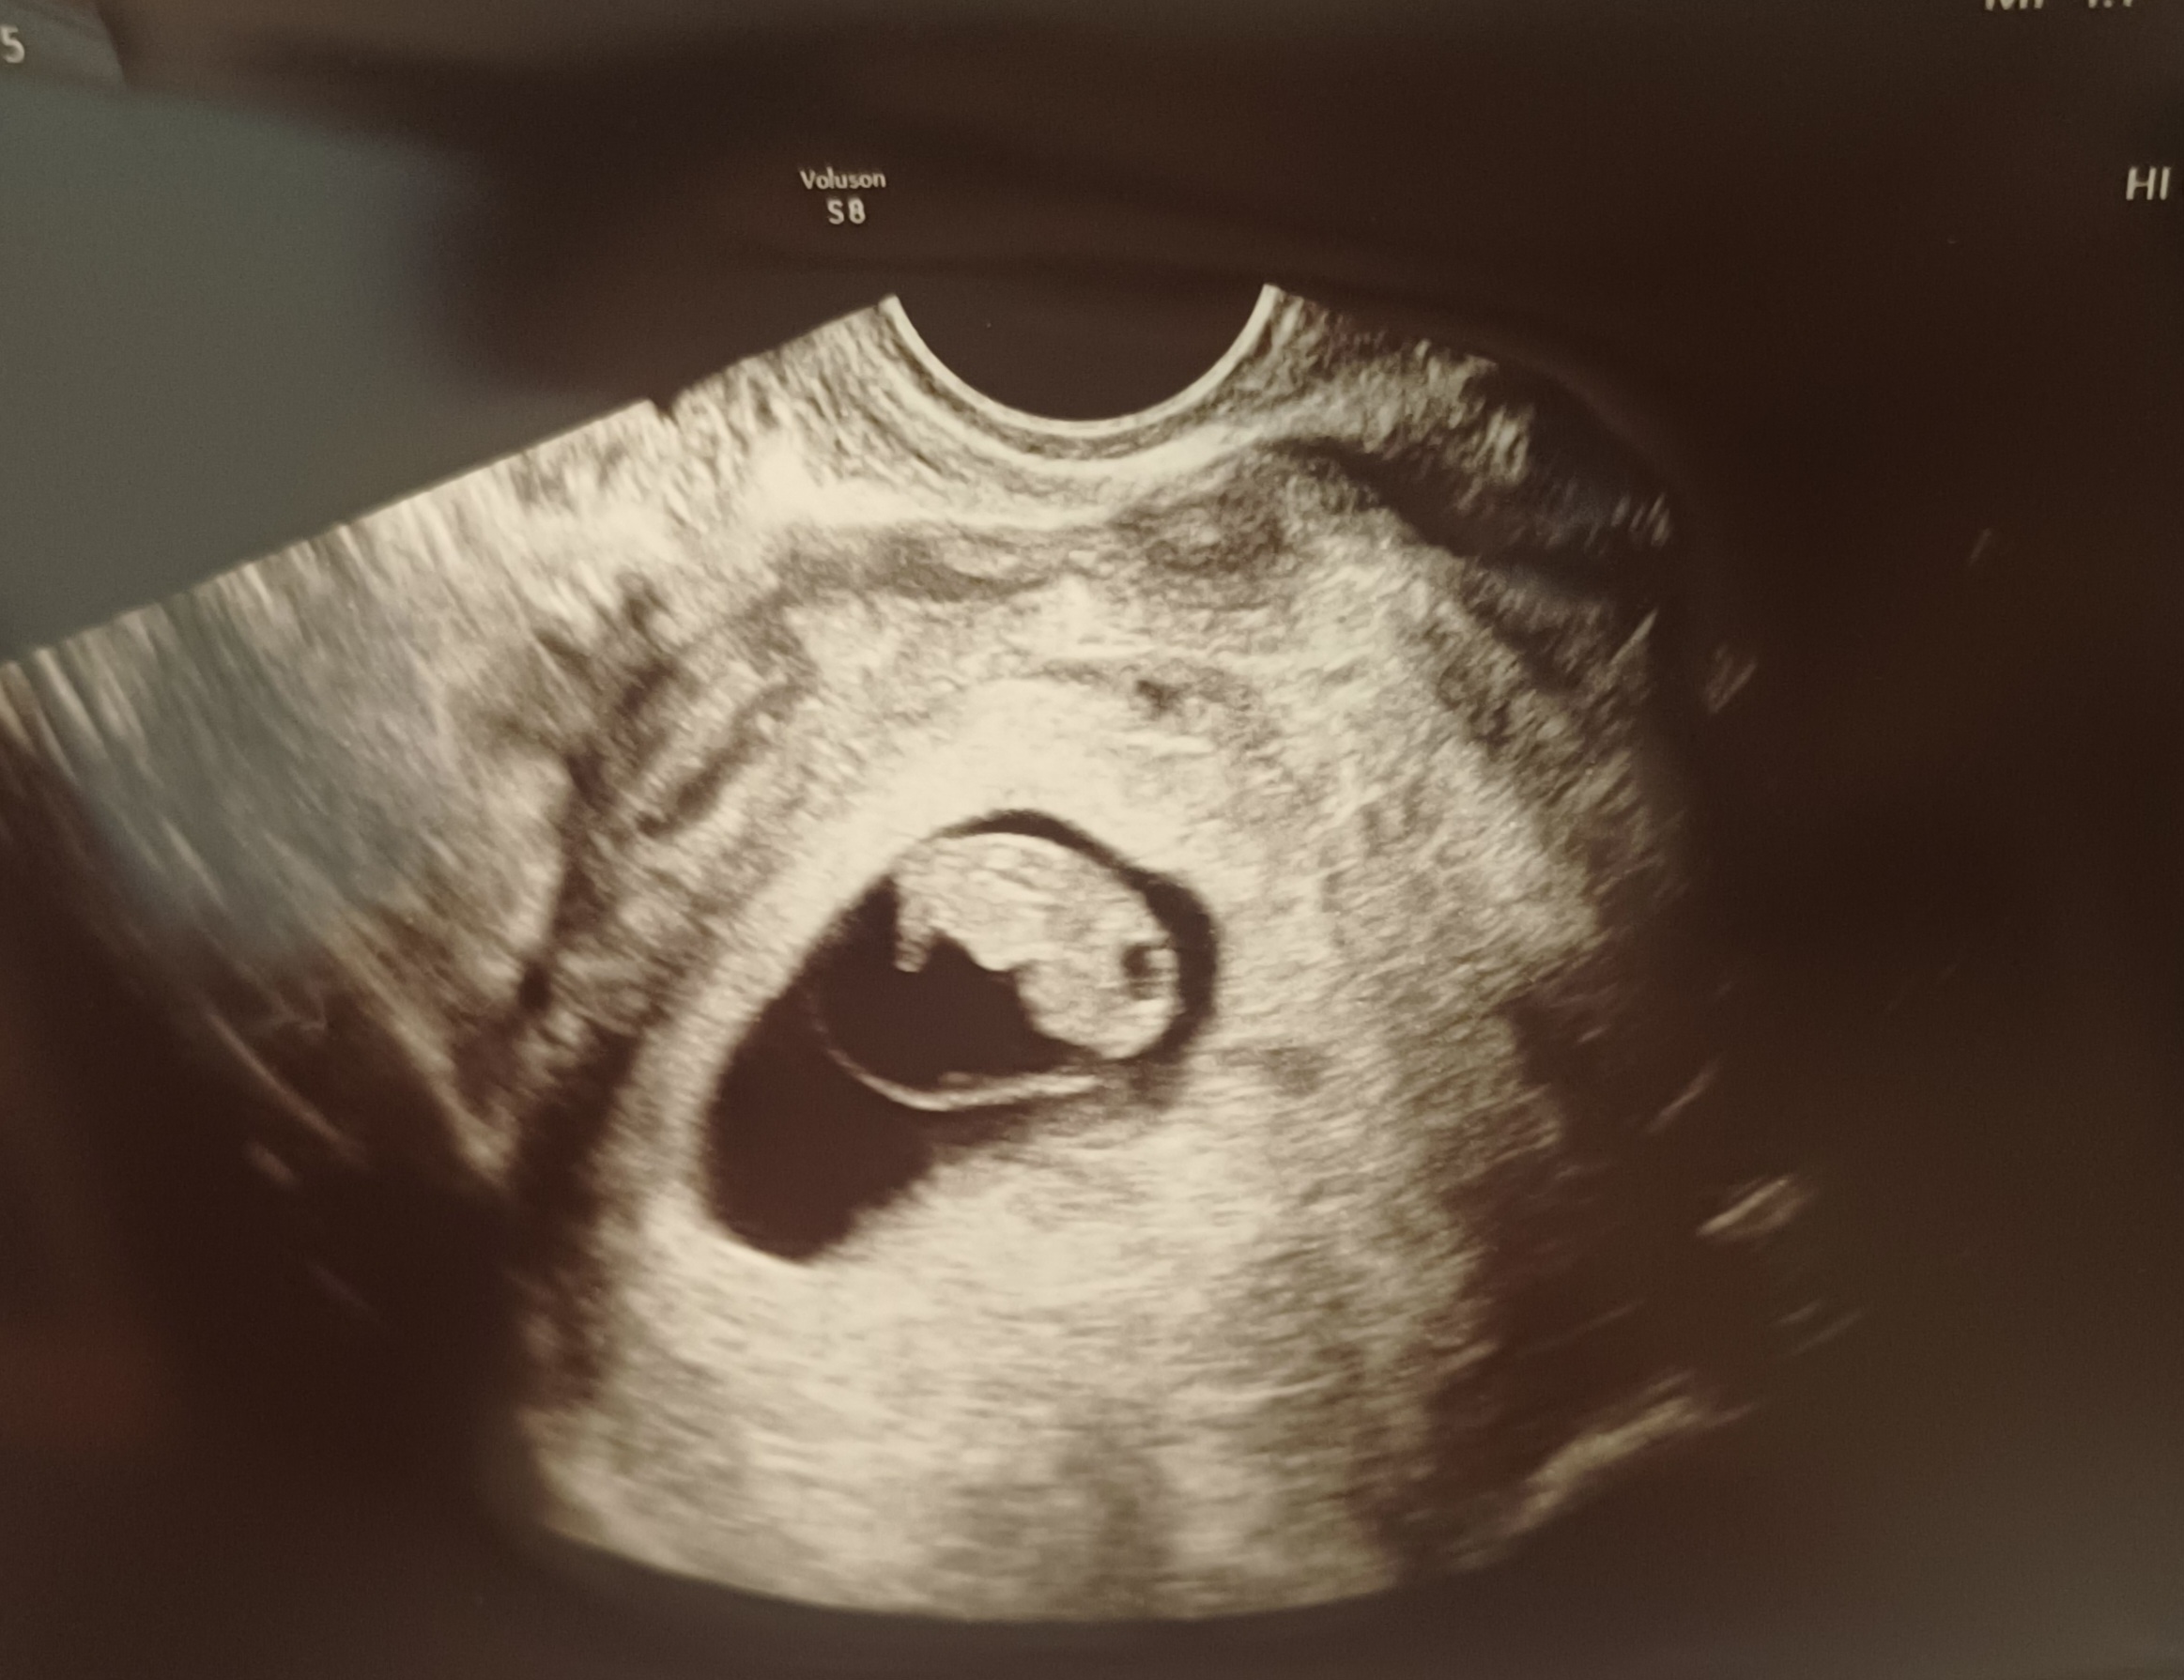

| 가슴 떨리는 임신 이야기를 공유해 주세요. | 오늘로 임신 10주차가 되었습니다. 운 좋게 시험관 첫 시도에 임신에 성공해 매일매일이 행복합니다. |

| 치료 도중 느꼈던 가장 기뻤던 순간과 절망적인 것들은 무엇인가요? 잊지 못할 경험이 있나요? | 가장 기뻤던 순간은 초음파에서 아기 심장소리를 들은 그날이었습니다. 우리 아기가 잘 있다는 확신이 들면서 마음이 놓이고 행복했습니다. 한편 가장 절망적이었던 순간은 피비침이 보였을 때였어요. 혹시나 하는 마음에 조마조마했지만, 초음파로 괜찮다는 확인을 받으며 마음을 놓을 수 있었습니다. |